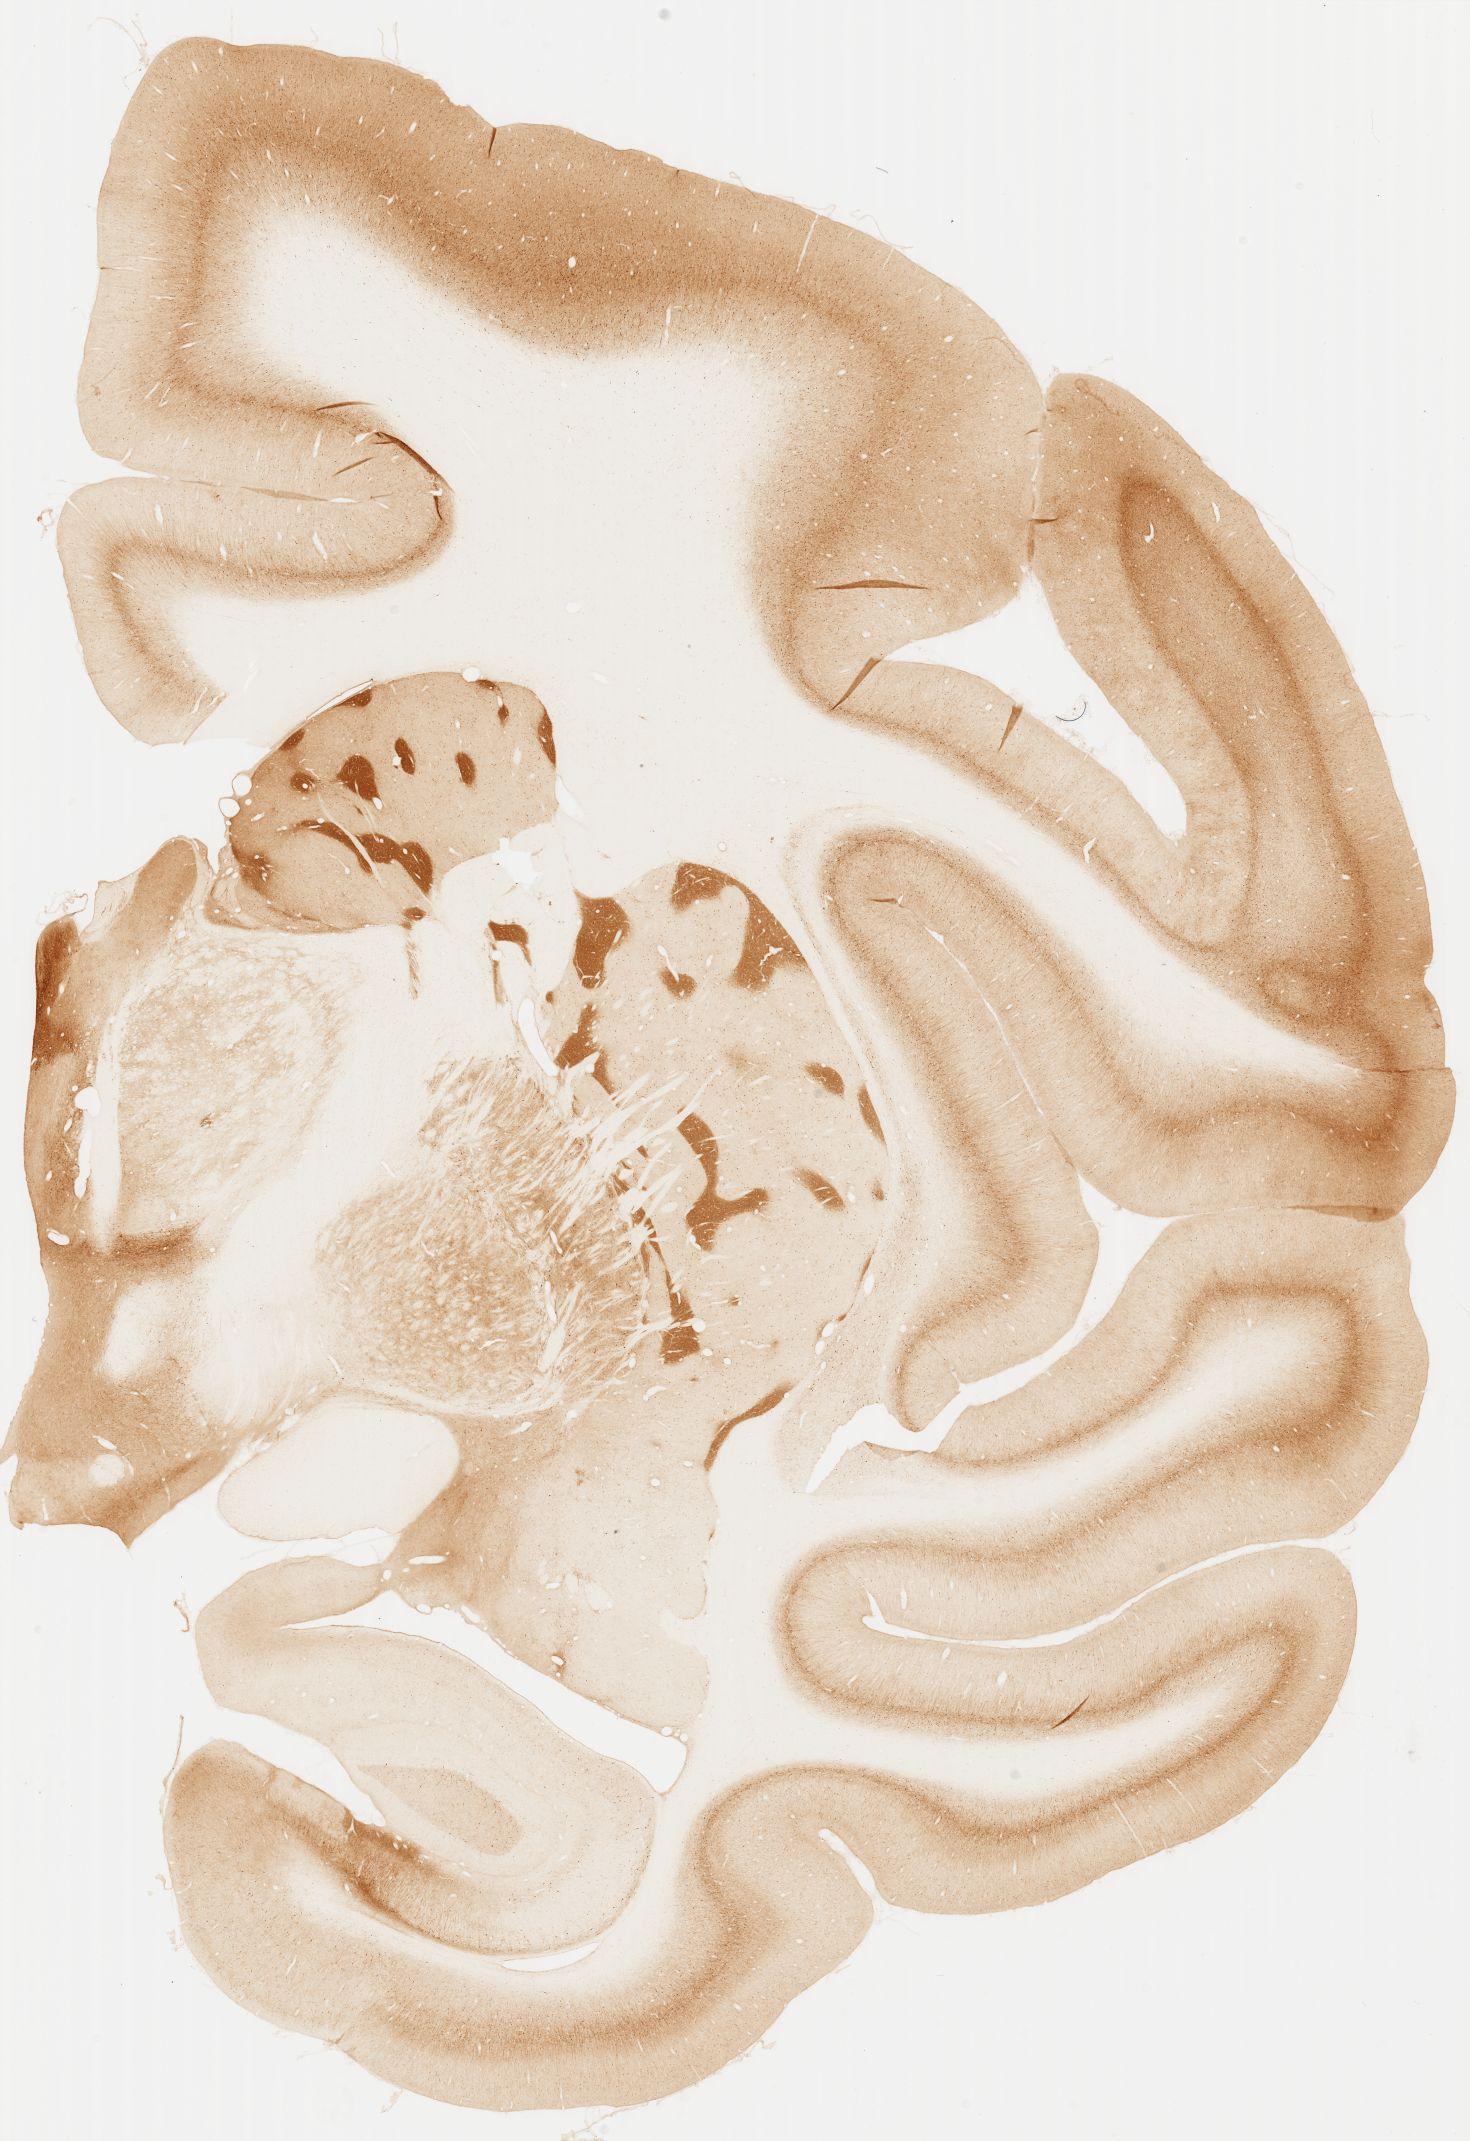

Datasets -> Macaca Fascicularis -> KChIP1, (Potassium Voltage-Gated Channel-Interacting Protein 1), coronal, immuno, Whole-Brain, adult

[ Metadata ]   ·   Source: Edward G. Jones

Displaying Sections 41 thru 80 of 92 Sections for this Dataset